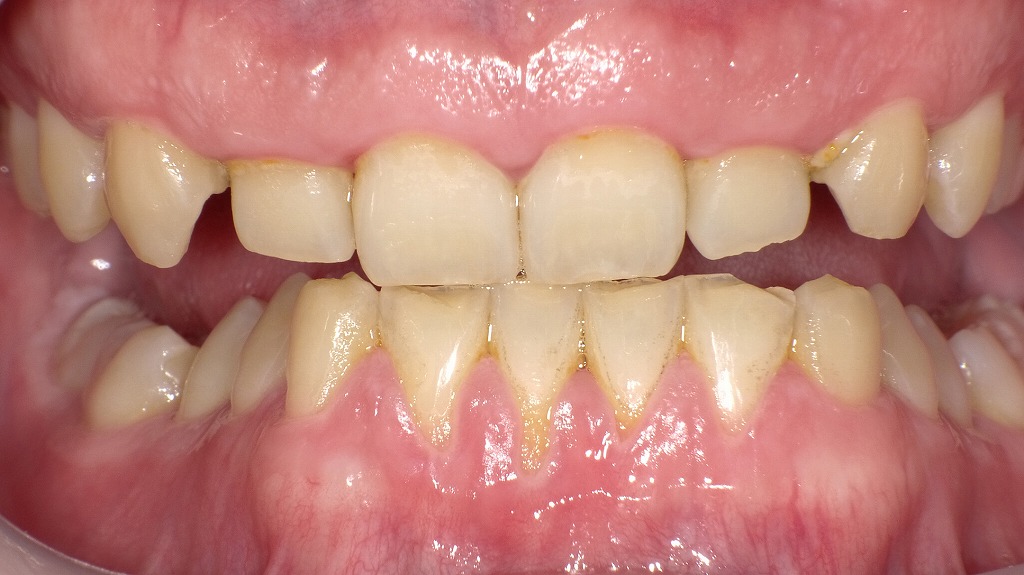

この画像は、歯が短く見える症例です。

- 歯が短く見える:

上顎前歯部は歯肉の被覆により、歯冠が短く見えています。 - 過蓋咬合(ディープバイト):

上の前歯が下の前歯を深く覆い、下の歯の露出が少ない過蓋咬合(ディープバイト)の症例です。通常より咬み込みが深いため、歯のすり減りや顎関節への負担が大きくなります。 - 下顎前歯切端の咬耗:

下の前歯の切端が平らにすり減っており、エナメル質が摩耗して象牙質が露出しています。咬耗による黄色みが見られます。 - 歯列・咬合のバランス:

上下の前歯の位置関係から**ブレーキフェイシャル(短顔型傾向)**が疑われます。

垂直的な咬み込みが強いことで、顔下半分が短く見える特徴があります。 - 歯の表面や歯間部に黄褐色の沈着物(歯石):

歯周組織にも影響を及ぼしていることがうかがえます。歯肉がやや赤く腫れぼったい状態で、**炎症性変化(歯肉炎〜初期歯周炎)**が疑われます。

この症例では、

- 過蓋咬合による強い咬耗(歯の摩耗)

- 歯石沈着と歯周病による歯肉炎症

が同時に見られます。

つまり、噛み合わせの異常によって清掃が難しくなり、結果として歯石や歯周炎が進行している可能性があります。

また、過蓋咬合による歯列の圧迫で、歯肉への局所的な負担も大きくなっていると考えられます。